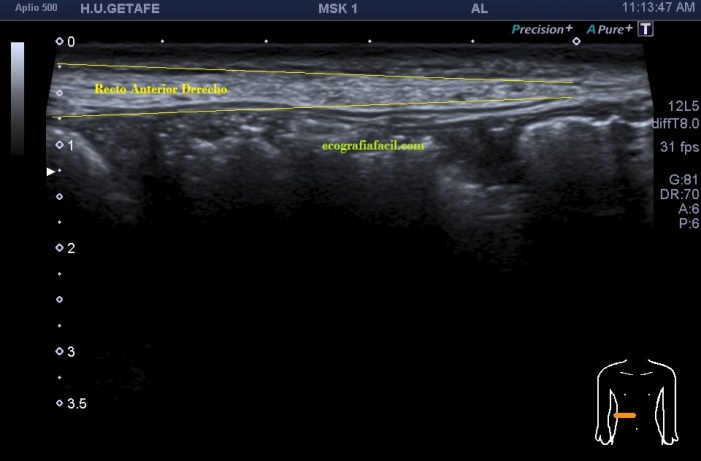

La imagen 1 es la ecografía anatómica que buscamos, los rectos anteriores a ambos lados de la imagen simétricos de aspecto hipoecogénico.

De la imagen 2 a 5 puedes ver los cuatro paquetes musculares pares que conforman la cara anterior del abdomen, lo que todos identificamos en esos cuerpos esculturales como la «tableta de chocolate». Cuando lo ecografiamos son igual de «sexys» si me permites la expresión, porque son muy bonitos, al ser simétricos su estudio es muy agradecido.

En la imagen 2 podemos ver el primer grupo muscular de los rectos abdominales donde ya observas como el lado derecho es ligeramente más pequeño que su lado izquierdo aunque la ecogenicidad es idéntica.